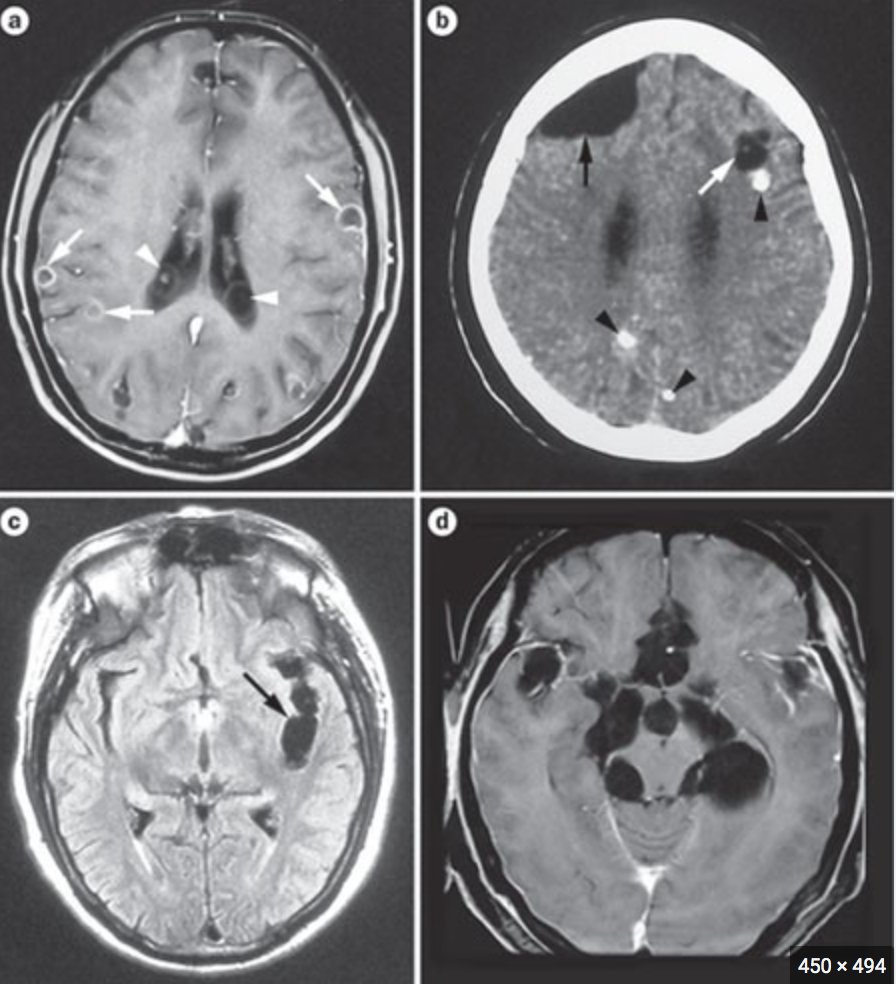

Tell me all about it, please? Lancet Neuro 2014.

viable vs non-viable. Source

nature review neuro